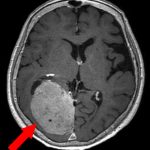

472

'23年10月

80代

円蓋部髄膜腫

頭蓋内腫瘍摘出術

No.’23_106 手術前1

No.’23_106 手術前2